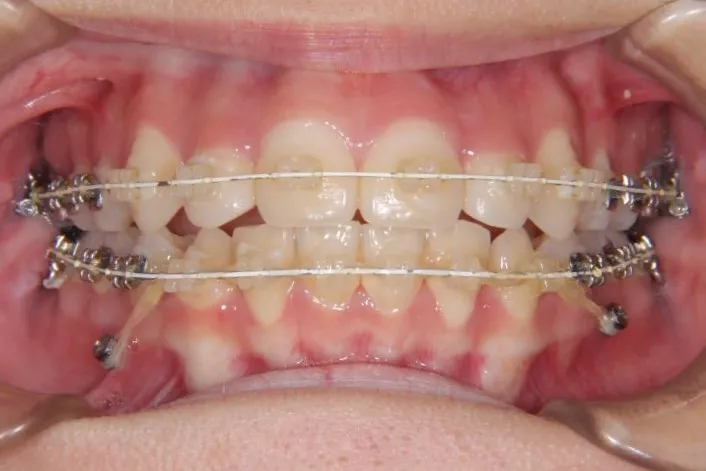

マルチブラケット装置

歯科矯正用アンカースクリュー

歯科矯正アンカースクリューを用いた治療で、非抜歯で口唇突出の改善、臼歯の圧下、叢生の解消を図りました。

治療回数34回、2年5ヶ月の治療期間で矯正治療を終了しました。

叢生は解消し、口元が大幅に引っ込み、下顎面高も縮小しました。

主訴が改善され、ご満足頂きました。